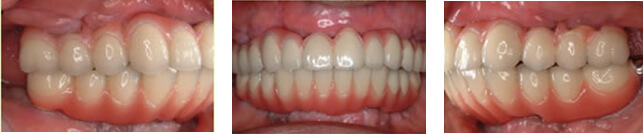

インプラント治療例その2(重度歯周病患者様、上顎に6本下顎に4本インプラント埋入、60歳代女性)

残念ながらここまで歯周病が広範囲かつ重度に進行してしまうと全て抜歯→総義歯が一般的な治療方針となりますが、患者様の強いご希望により必要最小限の本数を用いたインプラント治療によって、固定性補綴物による咀嚼回復が可能となりました。

暫間義歯を装着しCT撮影・診断の後インプラント埋入位置を決定、その位置へ正確に埋入するため作製されたサージカルガイドを用いて手術を行います。

術前

術後